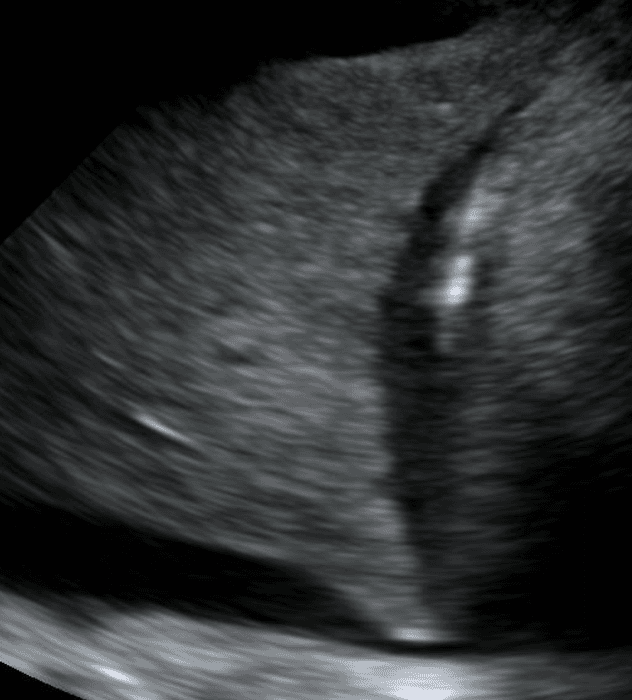

Consolidated lung appears dark due to its increased density and in some instances, may take on a similar texture to the liver. This is often referred to as “hepatization of the lung.”

Air bronchograms are air-filled bronchi that remain patent within the surrounding consolidated lung, They appear as hyperechoic structures within the hypoechoic consolidation. They may resemble multiple millimeter-long, lentil-shaped structures or branching tubular structures.

A shred sign represents the boundary between consolidated (abnormal) and aerated (normal) lung tissue. It appears as an irregular (shredded/fractal) line next to normal lung.